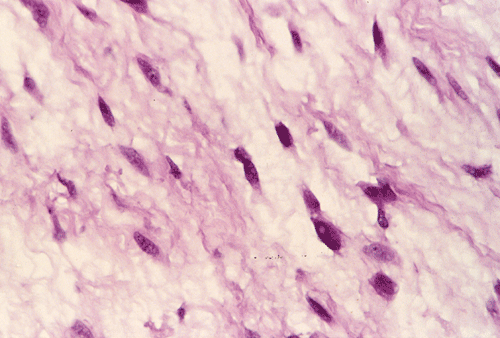

Panel A, B, and C are taken from the one area. Panel D, E, F, and G are taken from another area. Panel H and I are taken from areas with similar histologic features but distinctly separately on the same slide.

On low-magnifaction (Panel A and D), the lesional tissue appears to have generalized myomatous changes. No entrapped skeletal muscle fibers are found. The tumor cells tended to group into areas with variable cellularity that range from low- to, at most, moderate-cellularity. The hypocellular areas (Panel  B and C) contain sparsely spaced bland spindle cells in a bluish myxomatous background. The nuclei are elongated and mostly normochromatic. A few hyperchromatic nuclei are present and they are compatible with degenerative atypia (ancient change).